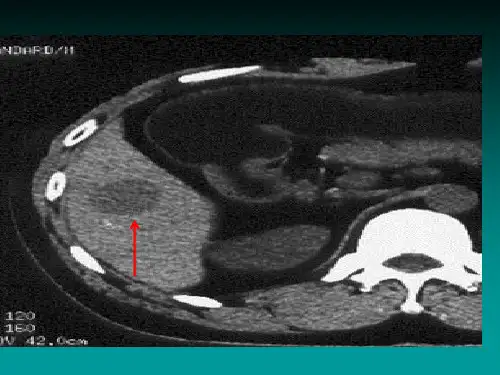

腹部CT扫描可见肝脏内低密度或高密度肿块,边界不清。

腹部CT扫描可见肝脏内低密度结节,增强扫描呈延迟强化。

肝脏血管瘤常呈多发性结节状病变,具有良好的强化性质,动脉期呈强化,门脉期和延迟期呈低密度。